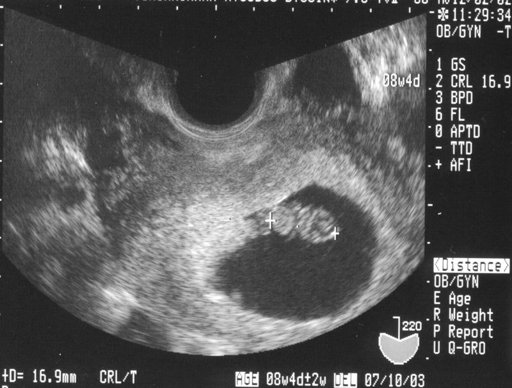

Thai 6 tuần tuổi vẫn còn rất nhỏ nhưng mẹ có thể nhìn thấy con mình thông qua hình ảnh siêu âm. Bên cạnh đó, những chỉ số của thai nhi sẽ cho biết em bé phát triển ra sao và có những vấn đề bất thường nào không. Đây là dấu mốc quan trọng của quá trình mang thai mà mẹ bầu cần hết sức lưu ý khi siê...

Khi biết mình mang thai, hẳn các ông bố bà mẹ đều vô cùng háo hức, mong muốn được nhìn những hình ảnh đầu tiên khi bé con còn đang nhỏ xíu. Do đó, kết quả siêu âm thai 6 tuần rất được mong đợi. Cha mẹ sẽ thấy được những hình ảnh đầu tiên của con, con phát triển như thế nào?

Khi được 6 tuần tuổi, thai nhi đang phát triển nhanh chóng để hoàn chỉnh phôi thai. Lúc này, con có kích thước khá nhỏ và chỉ có thể nhìn thấy được thông qua hình ảnh siêu âm. Vậy ngoài việc quan sát sự phát triển của con, thì siêu âm thai 6 tháng còn có ý nghĩa gì nữa?